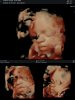

Hej! My dziś po lekarzu.

29+5, Lenka waży 1283g. Zdrowa dziewczynka 🥰 policzyliśmy paluszki i obejrzeliśmy każdy kawałek ciałka.

Jeśli chodzi o wyprawkę to mamy już praktycznie wszystko dla córki, jeszcze muszę nakupowac "wyprawkę" do siebie 🙈

Załączniki

• IMG_20201119_134256.jpg

IMG_20201119_134256.jpg

319,4 KB · Wyświetleń: 77